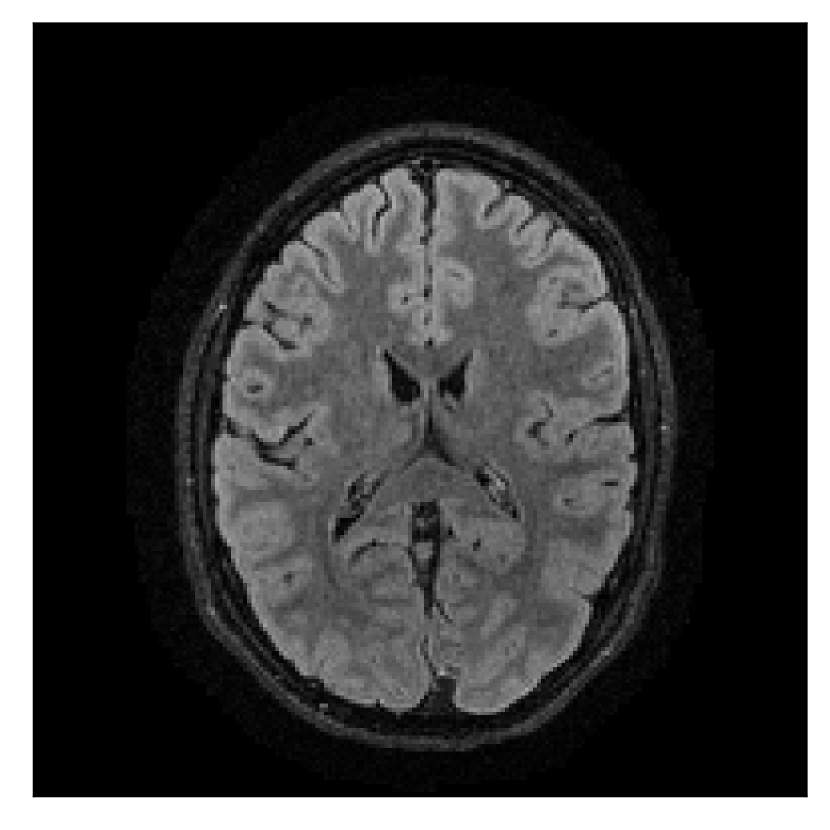

4.1 Experiment 1: robustness test

We gather the results for the robustness test described in Section 3.1 (volunteer 1) in Figures 2, 4, and 6 for motion corruption mechanisms associated to one, two, and five changes of position, respectively. Furthermore, we juxtapose the corrected images with varying degrees of corruption in Figure 8. We observe that the proposed method consistently ameliorates the corrupted scan. The quality indexes based on PSNR and SSIM show only a modest decrease in correction quality as a function of motion complexity (Figure 8).

| Section 3.1, Figure 2 | Sagittal | 23.94 | 27.95 | 0.7068 | 0.7936 |

| Coronal | 26.66 | 29.82 | 0.7653 | 0.8332 | |

| Axial | 25.40 | 30.16 | 0.7616 | 0.8490 | |

| Section 3.1, Figure 2 | T2-FLAIR | Completely corrected | Some blurring | No additional artifacts | Good grey white matter differentiation |